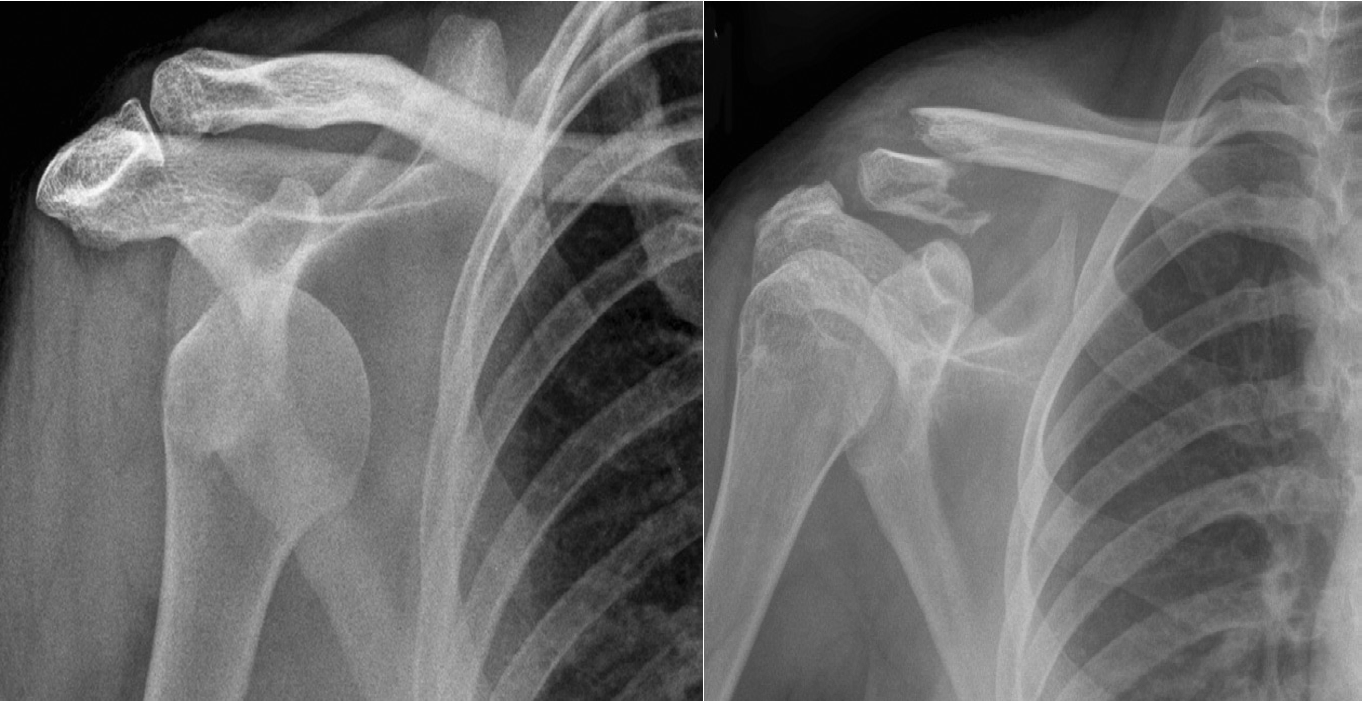

Anterior dislocation of the shoulder. - Fracture of the clavicle The head of the humerus is displaced inferior and anterior to the glenoid fossa to lie beneath the coracoid process.

with  upward displacement of the medial fragment is frequently seen, as in this example. in second image